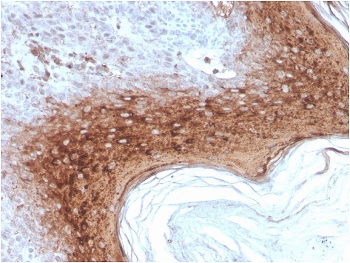

IHC staining of FFPE human skin with recombinant Involucrin antibody (clone rIVRN/827J). HIER: boil tissue sections in pH 9 10mM Tris with 1mM EDTA for 20 min and allow to cool before testing.

It recognizes a protein of 66kDa-170kDa, identified as involucrin. In Western blotting of cultured human keratinocytes, this MAb reacts with a 120kDa protein. It stains the involucrin in a variety of sizes: 170kDa in MCF-7 cells, a doublet of ~115kDa and 150kDa in gorilla and owl monkey, 66kDa in dog, and a doublet of 105kDa in pig. Its epitope maps between codon 421-568 of human involucrin. Involucrin is expressed in a range of stratified squamous epithelia, including the cornea, which lacks a distinct cornified layer. In normal epidermis, it is first expressed in the upper spinous layers, and in keratinocyte cultures, all cells that have left the basal layer express it. Involucrin expression is altered in pathological conditions: in psoriasis and other benign epidermal hyperplasias, involucrin expression begins closer to the basal layer than normal; expression is abnormal in squamous cell carcinomas and premalignant lesions, and is reduced in severe dysplasias of the larynx and cervix.